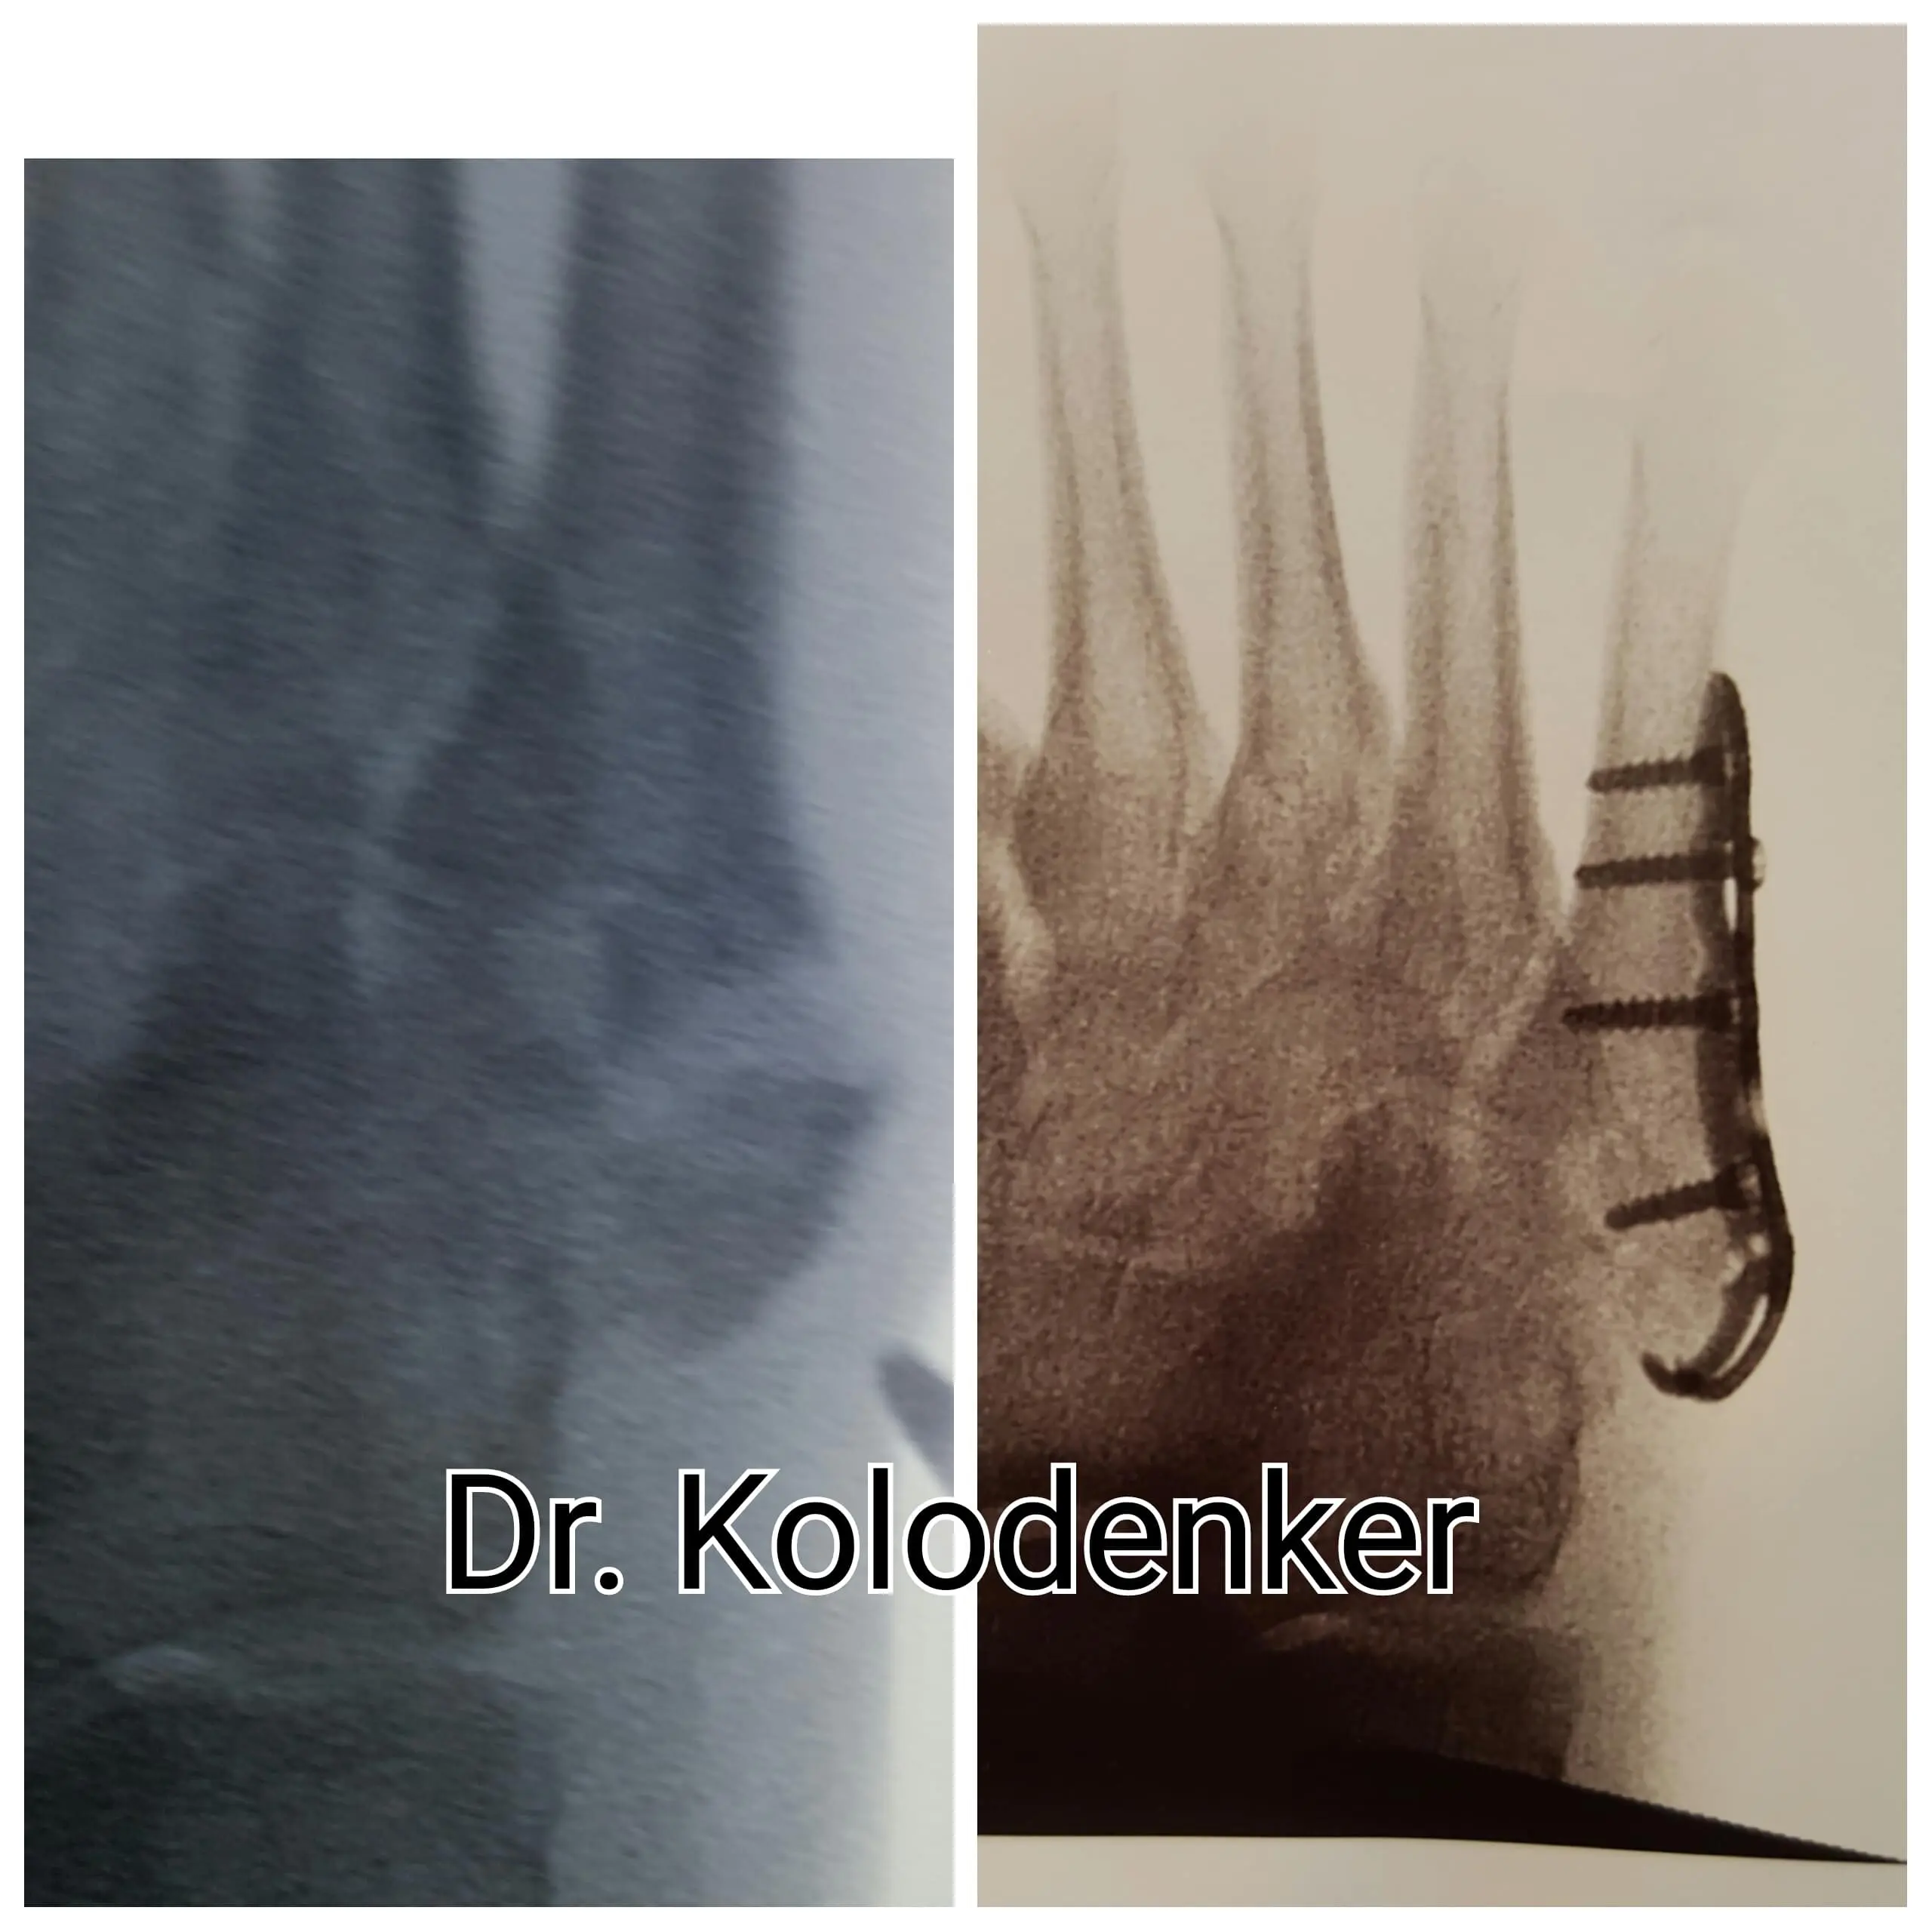

Surgical treatment of Posterior Tibial Tendon Dysfunction in Orange County

Done when conservative treatment has failed to improve symptoms.

Surgery involves repairing the tendon and realigning the bones of the foot.

The arch must be recreated for the procedure to have long term relief.